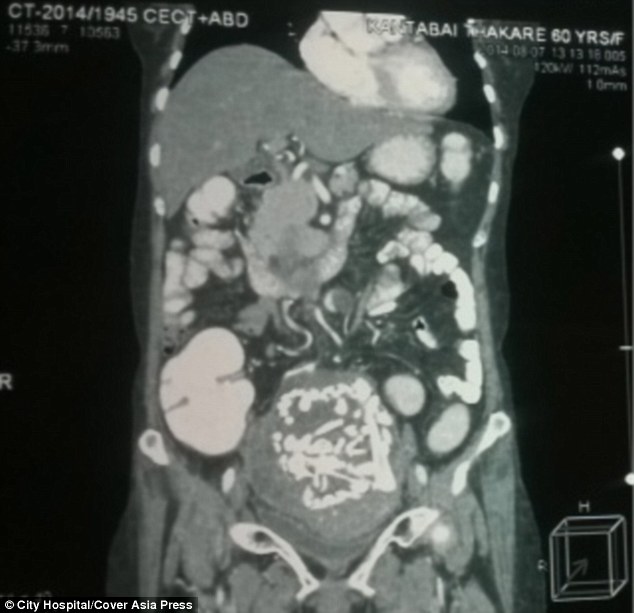

5. Tulang belulang

Benda ini ditemukan dalam perut seorang ibu berusia 60 tahun asal India, Kantabai Thakre. Tulang-tulang ini merupakan milik bayi yang dikandungnya 36 tahun lalu ketika dia berusia 24 tahun.

Sang ibu takut operasi mengangkat bayinya yang tumbuh di luar rahim dan tidak berhasil dilahirkan itu, sehingga memilih berobat ke klinik kecil yang akhirnya menyisakan tulang belulang di tubuhnya.